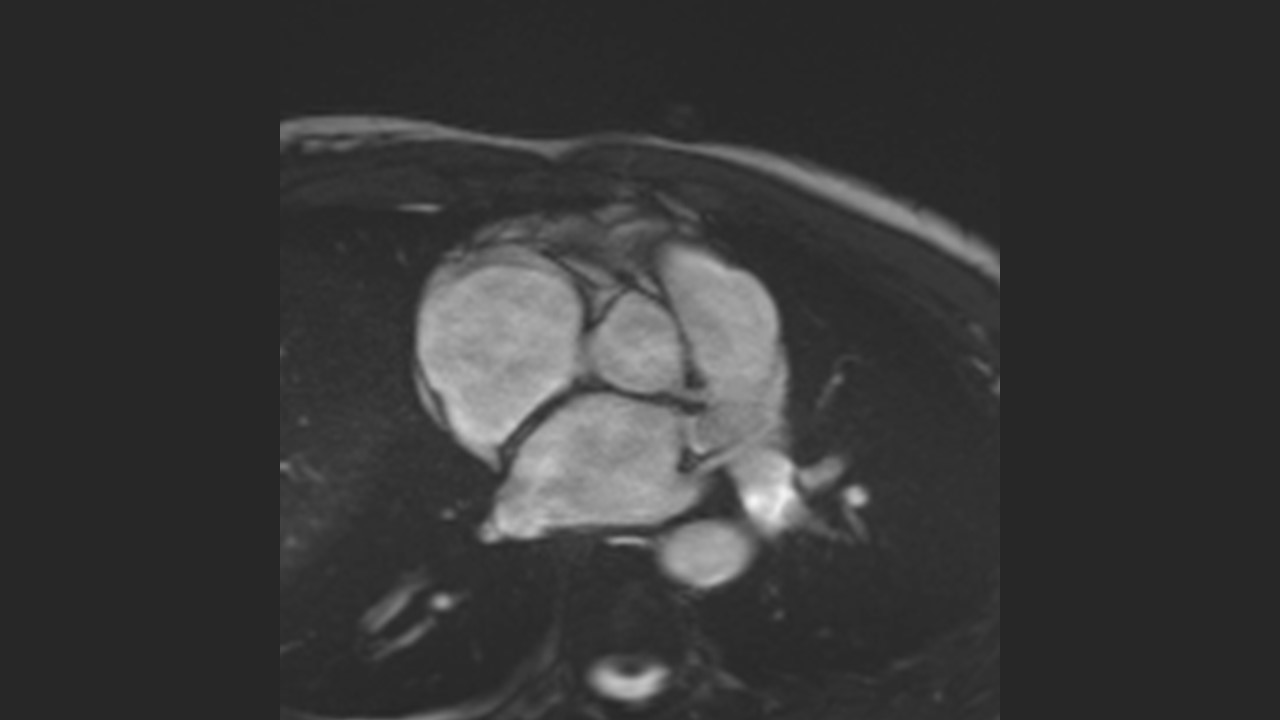

Sinuses of Valsalva

Aortic Root Series